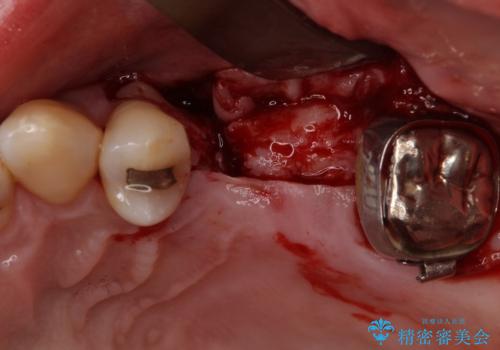

ブリッジの支台を抜歯したことで2本のインプラントが必要であり、その後方はインプラント埋入に必要な骨量が不足していたため、上顎洞粘膜の挙上を行うこととしました。

また、残っている最後方歯は手前に倒れてきていたため、部分矯正により奥に移動させてから、インプラント埋入を行うこととしました。

部分矯正期間中はアンカースクリューやフック、ゴムなどが粘膜にあたり、大変な思いをすることになりましたが、そのおかげでインプラント補綴した歯と最後方歯の位置が非常に良好となり、まるでご自身の歯のように咬むことができるようになりました。